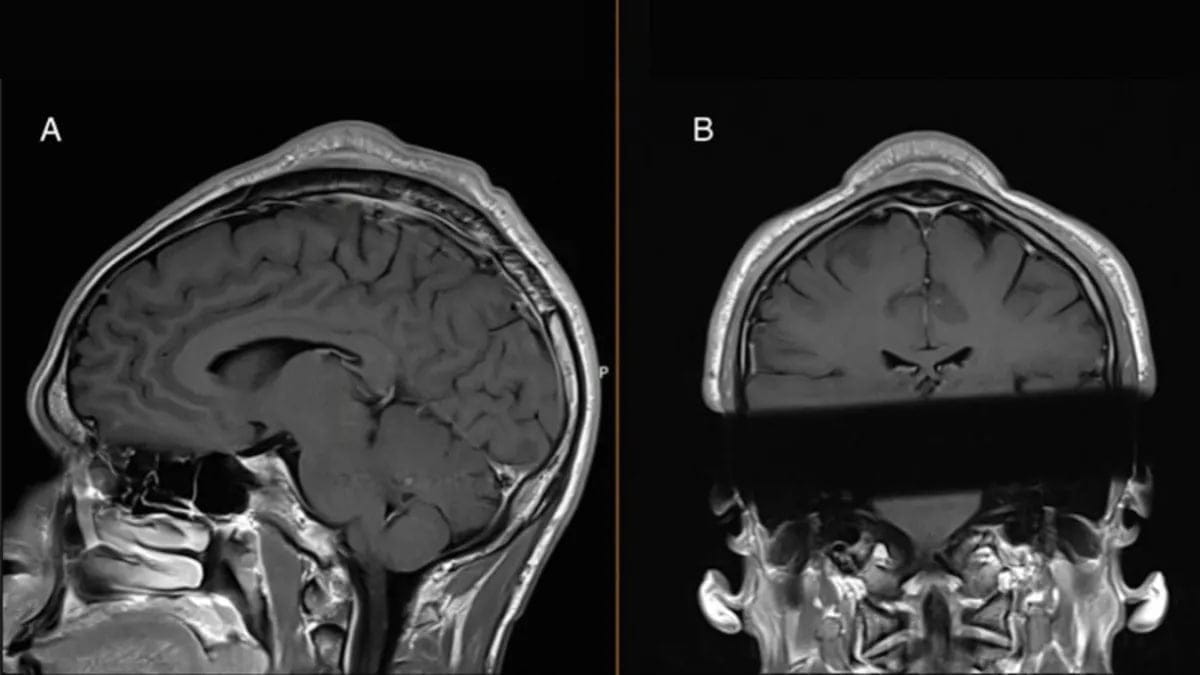

Лікарі, які оглядали пацієнта, зазначили, що шкіра над опуклістю легко рухалася, що свідчило про те, що маса тканини розташована між шкірою та черепом. Структурне сканування голови підтвердило цей діагноз, виявивши, що шкіра над опуклістю та кістка черепа під нею стали товщими у порівнянні з навколишніми тканинами.

Знімок

Фото: BMJ Case Reports 2024